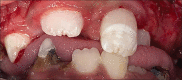

Surgical management of maxillary trauma in pediatric special needs patient using modified cap splint

Pediatric maxillofacial trauma is a rare entity, which is primarily the reason for an individual surgeon's inexperience in managing such injuries. More so, maxillary injuries are infrequent. Pediatric maxillofacial injuries are usually a result of blunt force trauma such as falls, motor vehicle accidents, bicycle injuries, sports-related injuries, assault, and child abuse. The atypical pattern of facial injuries in the pediatric population necessitates each surgeon to approach individual cases with a unique and innovative technique of management, while still following the basic principles of surgical management of maxillofacial injuries. Since facial trauma and surgical interventions both have the potential to lead to disturbance in growth and development, management should be as conservative as possible. The foundation of any surgical intervention must be developed keeping in perspective, the future growth, and development of dentofacial structures. Pediatric facial trauma management is in itself a disconcerting situation for a maxillofacial surgeon, but when a special needs child is involved it becomes an even more perplex decision. We present a case of maxillary trauma in a pediatric patient with global developmental delay, the treatment dilemma, and a review of current literature.